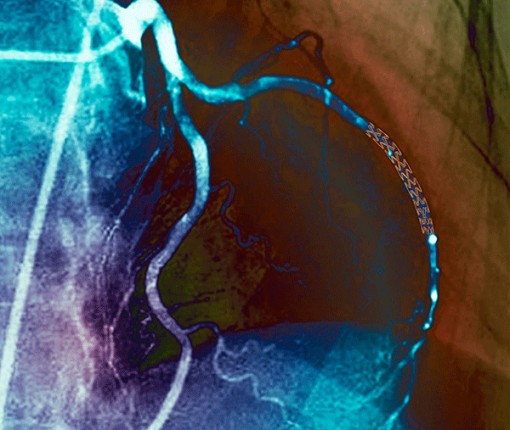

Thuốc điều trị hẹp mạch máu hiệu quả như phẫu thuật xâm lấn

15 phút cứu sống nam thanh niên 23 tuổi ngưng tim

(CTO)- Sáng 18-11, bác sĩ Phạm Thanh Phong, Phó Giám Đốc chuyên môn Bệnh viện Đa khoa Trung ương Cần Thơ cho biết, trung tâm tim mạch bệnh viện vừa cứu sống một bệnh nhân nam 23 tuổi nhồi máu cơ tim tối cấp có biến chứng ngừng tim. Đến sáng 18-11, bệnh nhân sinh hoạt gần như bình thường.